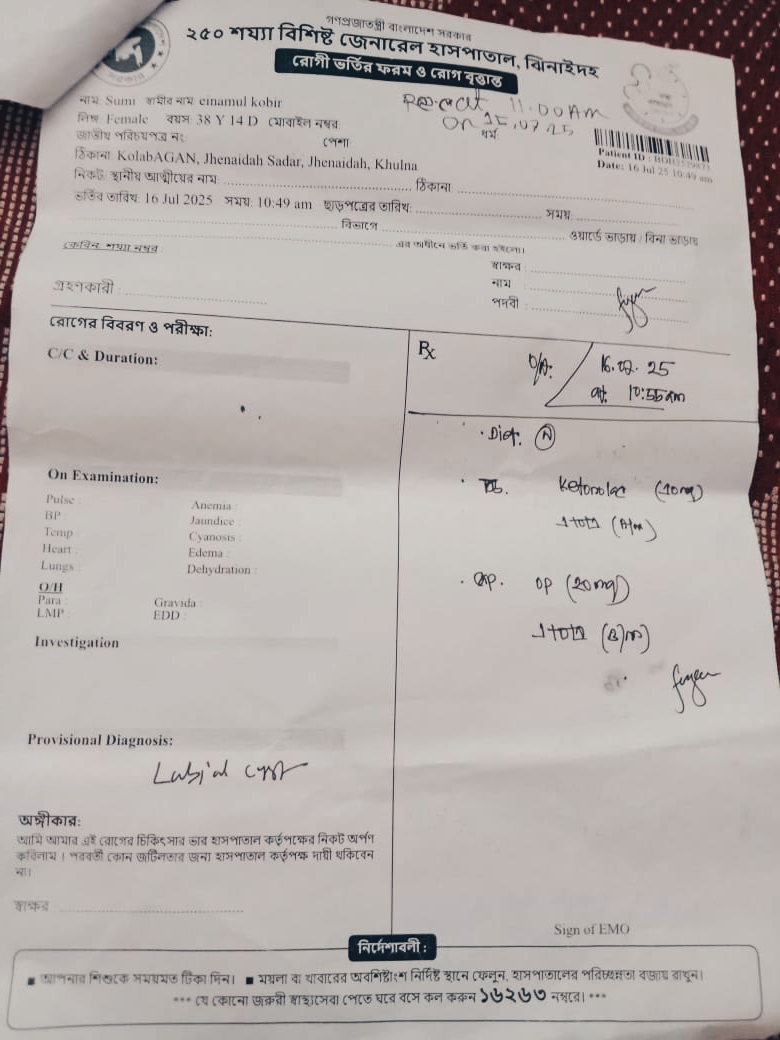

#250928D: তহুরা খাতুনের টিউমার অপারেশনের জন্য সাহায্যের হাত বাড়িয়েছেন; গ্রাম: কলাবাগান, জেলা: ঝিনাইদহ।